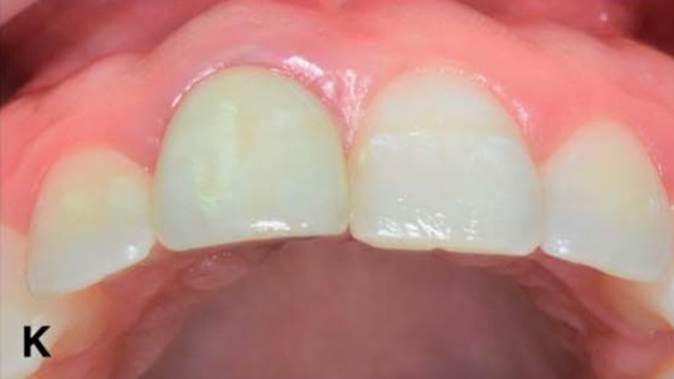

“Immediate loading of single AnyRidge implants

is a highly successful treatment modality. ”

Clinical case: Immediate post-extraction insertion of implant & immediate loading

- Courtesy of Prof. Giuseppe Luongo, Italy -

AnyRidge, immediate loading, single implant, multicenter study, maxillary anterior, Prof. Giuseppe Luongo, single replacement

AnyRidge implant system

Immediate functional loading of single implants: a multicenter study with 4 years of follow-up

/J Dent Res Dent Clin Dent Prospect 2018; 12(1):26-37 | doi: 10.15171/joddd.2018.005

https://www.ncbi.nlm.nih.gov/pubmed/29732018